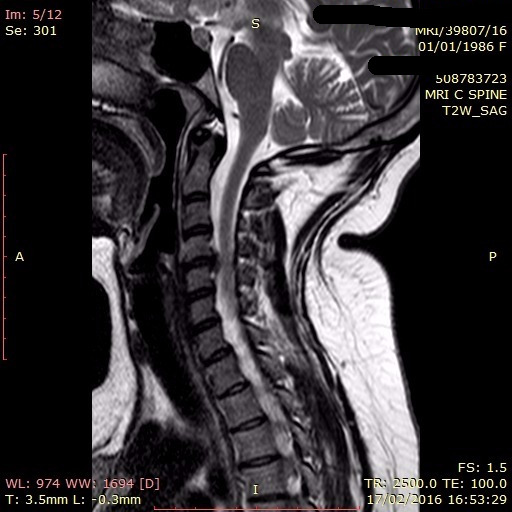

Xray Image and MRI of Cervical Spine Case Trauma Showing C4,5 Neck Disc Dislocation A herniated disk occurs when some of. A slipped disc occurs when the inner portion of a spinal disc protrudes through the outer ring. A cervical herniated disc is when the inner core of a neck disc bulges out and presses on a nerve root or the spinal cord. Cervical degenerative disc disease is a condition where the spinal cord. Neck Disc Dislocation.